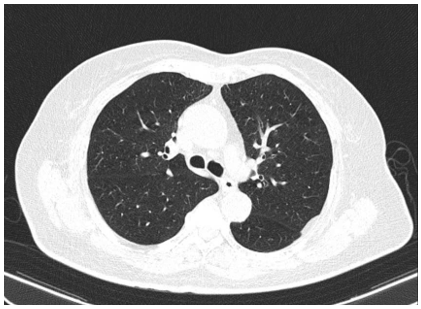

- Chụp CT lồng ngực không tiêm thuốc cản quang:

Hình 5: Hình ảnh CT lồng ngực không tiêm thuốc cản quang chưa phát hiện bất thường